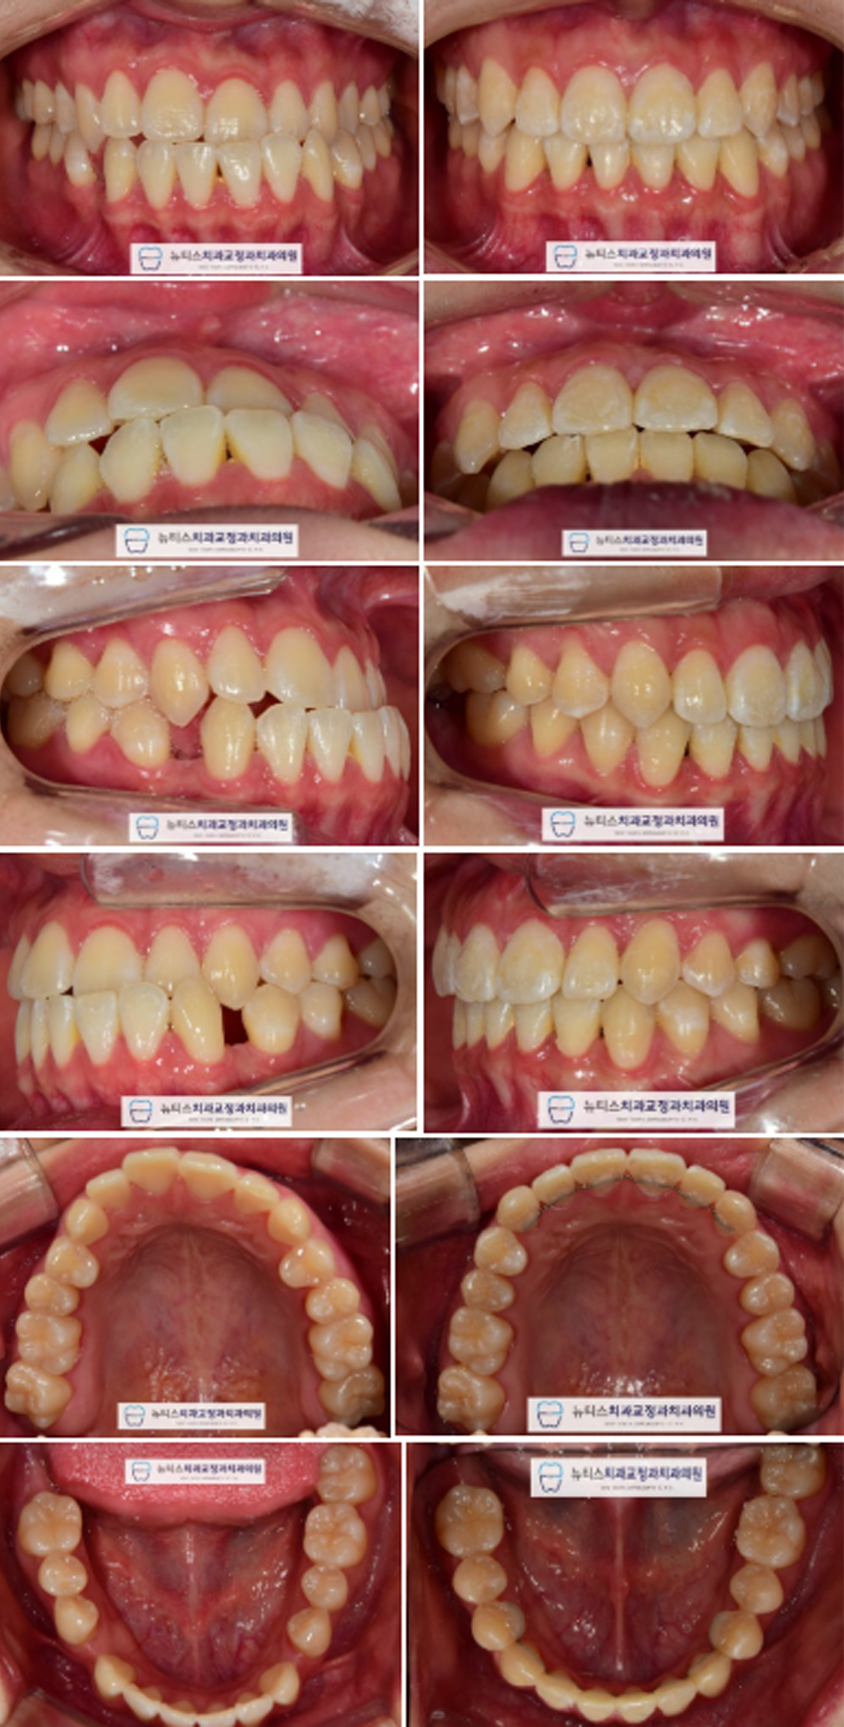

±³Á¤ ÀåÄ¡¸¦ ºÎÂøÇÏ°í ¹è¿ÇÏ´Â ÁßÀÔ´Ï´Ù.

#¹Ý´ë±³ÇÕ À» º¸ÀÌ´ø Ä¡¾Æ°¡ °³¼±µÇ°í ÀÖÀ¸³ª

¾Æ·¡ÂÊ¿¡ ³²¾ÆÀÖ´Â Æ´Àº ¿©ÀüÈ÷ Á¸ÀçÇÕ´Ï´Ù.